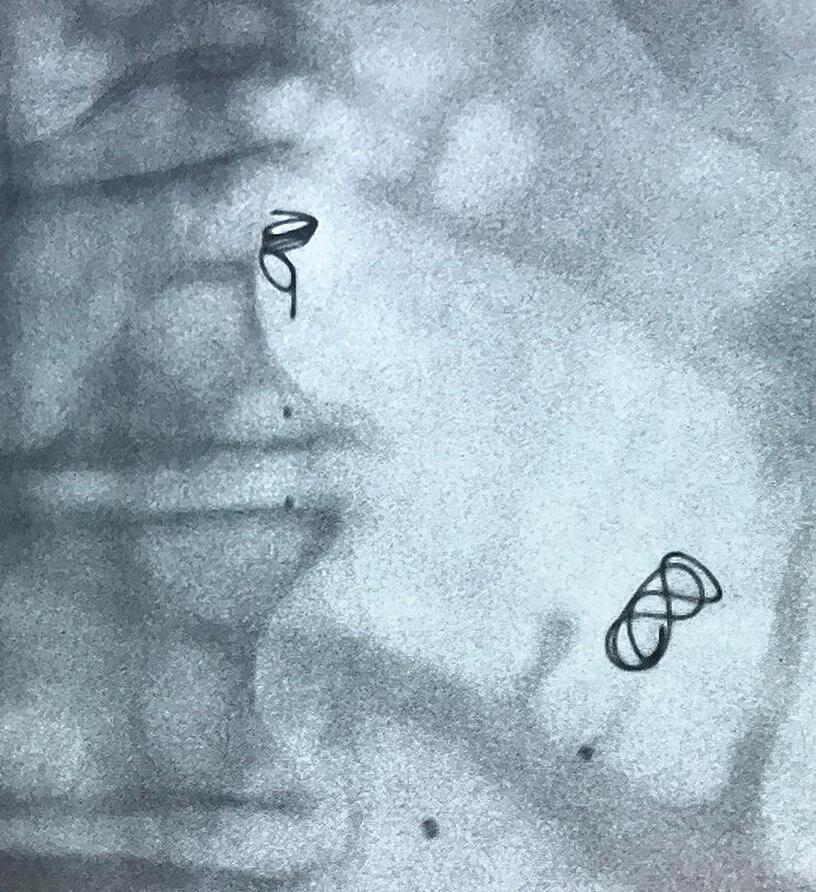

INDICATION: The IMPEDE Embolization Plug is indicated to obstruct or reduce the rate of blood flow in the peripheral vasculature. INDICATION: The IMPEDE-FX Embolization Plug is indicated for use with the IMPEDE Embolization Plug to obstruct or reduce the rate of blood flow in the peripheral vasculature. CAUTION: Federal (U.S.A.) law restricts this device to sale by or on the order of a physician. Indications, contraindications, warnings and instructions for use can be found in the product labeling supplied with each device. Inferior Mesenteric (IMA) and Renal Accessory Artery angiographic image courtesy of Alexander Maβmann, MD, Saarland University Medical Center, Homburg/Saar, Germany. The images are illustrative and do not represent the actual size of any products. Shape Memory Medical and IMPEDE are registered trademarks of Shape Memory Medical. The shape memory polymer advantage is clear Beyond embolization www.shapemem.com LIT1134 Rev A IMPEDE® Embolization Plug IMPEDE-FX Embolization Plug

to the anatomy

Conforms

new healing possibilities

material restores unprecedented visibility

and after the procedure Returns clarity

Delivers unmatched volume Generates

Radiolucent

during